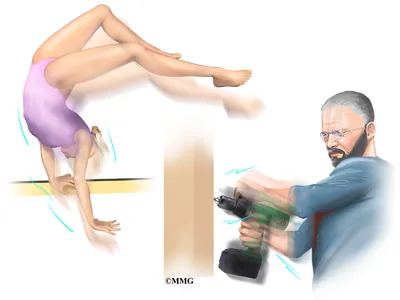

Triangular fibrocartilage complex (TFCC) injuries affect the ulnar side of the wrist—the side closest to the little finger. Mild cases may feel like a simple wrist sprain, but due to the complexity of the wrist’s soft tissues, these injuries can significantly impact stability and function.

The TFCC plays a crucial role in supporting and stabilizing the wrist joint, allowing smooth and controlled movement. When this structure is damaged through trauma or gradual degeneration, it can lead to persistent pain, weakness, and limited mobility.